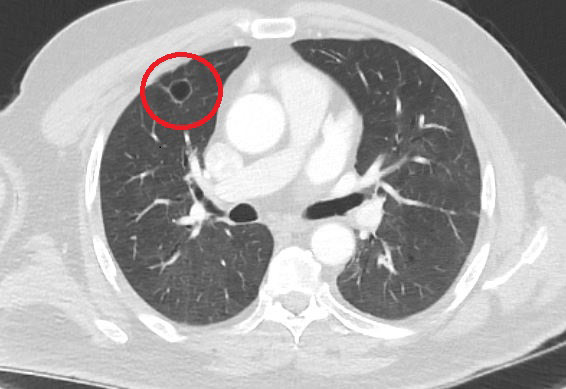

Kahramanmaraş'ta kent dışında çalışan N.T.'nin (52), göğüs ağrısı şikayetiyle gittiği hastanede çekilen tomografisinde sağ akciğerinde 4 santimetre çapında tümör tespit edildi.

Kanser olabileceği şüphesiyle yapılan ileri tetkikler sonrası N. T.'ye akciğer kanseri teşhisi konuldu ve acil ameliyat kararı verildi. Bunun üzerine N.T. ameliyat için memleketi Kahramanmaraş'a geldi. Sütçü İmam Üniversitesi Sağlık Uygulama ve Araştırma Hastanesi Göğüs Cerrahi Anabilim Dalı Öğretim Üyesi Dr. Fatoş Kozanlı da tomografi ve test sonuçlarına göre N. T.'ye akciğer kanseri teşhisi koydu ve ameliyat yapılması gerektiğini söyledi.

Ameliyat öncesi N.T.'nin Kovid-19 testi pozitif çıkınca operasyon ertelendi. Koronavirüs tedavisine başlanan N.T.'nin son testi negatif çıktı. Dr. Fatoş Kozanlı, tedavi sonrası tomografisi çekilen N.T.'nin akciğerindeki tümörün yok olduğunu gördü. Kozanlı, N.T.'nin kendilerine başvurduğunda koronavirüs belirtisi olmadığını ancak ameliyat öncesi PCR testi yaptıklarını söyledi. Koronavirüs tedavisinin ardından ortaya çıkan sonucun kendisini de şaşırttığını belirten Kozanlı, şunları söyledi:

"Hasta bize başvurdu ve göğüs ağrısı şikayeti vardı. Öksürük, nefes darlığı, balgam çıkarma, ateş gibi şikayetleri yoktu. Hastayı biz de değerlendirdik ve ameliyat olmasına karar verdik. Çünkü akciğer kanserine çok benzer radyolojik bulguları vardı. Sağlık Bakanlığımızın kuralları gereği her hastayı ameliyat öncesi PCR testi yapılır. Biz de ameliyat gecesi hastadan PCR testi aldık ve testi pozitif geldi. Ameliyatımızı 14 gün erteledik ve hastamıza koronavirüs tedavisi uygulandı. Hasta 14'üncü gün tekrar bize başvurdu ve yapılan PCR testi negatif çıktı. Yeni bir tomografi çektik ve tümörün tamamen ortadan kalktığını gördük. Şimdi sonuç bilgilerinden başlangıca gittiğimizde, bu bir akciğer kanseri olsaydı, ortadan kalkması mümkün değildi. Başka bir patolojiye bağlı durum olsaydı, yine verdiğimiz tedaviyle ortadan kalkmasını çok beklemeyiz. Antiviral tedavisi verdik ve hastanın radyolojik bulguları neredeyse tamamen normale döndü. Hastaya bunu izah ettik, 'Dünya literatüründe hiç görülmeyen bir radyolojik bulgu' diyerek. Bu gördüğümüz manzara artık hastanın akciğer grafisinde yok, akciğer kanseri değil. "